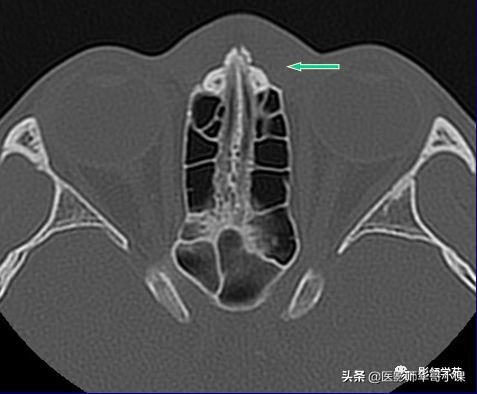

线性骨折 粉碎骨折

左侧鼻骨线形骨折

右侧鼻骨骨折

左上颌骨额突骨折

双侧鼻骨骨折

双侧上颌骨额突骨折